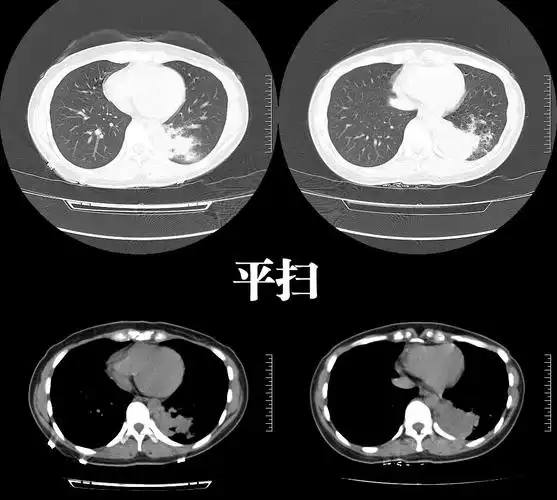

肺隔离症影像表现_郑孝飞

右肺下叶肺隔离症一例-中国期刊网

年轻女子咳嗽,咳痰2年,病因不寻常……_肺隔离症_医脉通

肺隔离症

肺隔离症诊断之影像与病理